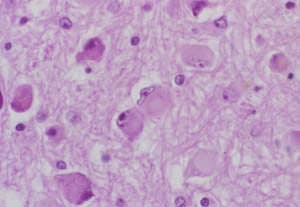

Kronik Hepatit

Kronik (Süreğen) Karaciğer Hastalığı Karaciğer dokusunun zaman içinde yavaş yavaş yıkımıdır. Karaciğer sirozu ve karaciğer fibrozisi gibi pek çok...

Kronik (Süreğen) Hepatitler: Bir çok nedene bağlı olarak karaciğerdeki iltihabi sürecin en az 6 ay sürmesine denir. Yaş: Kronik hepatit nedenlerinden...